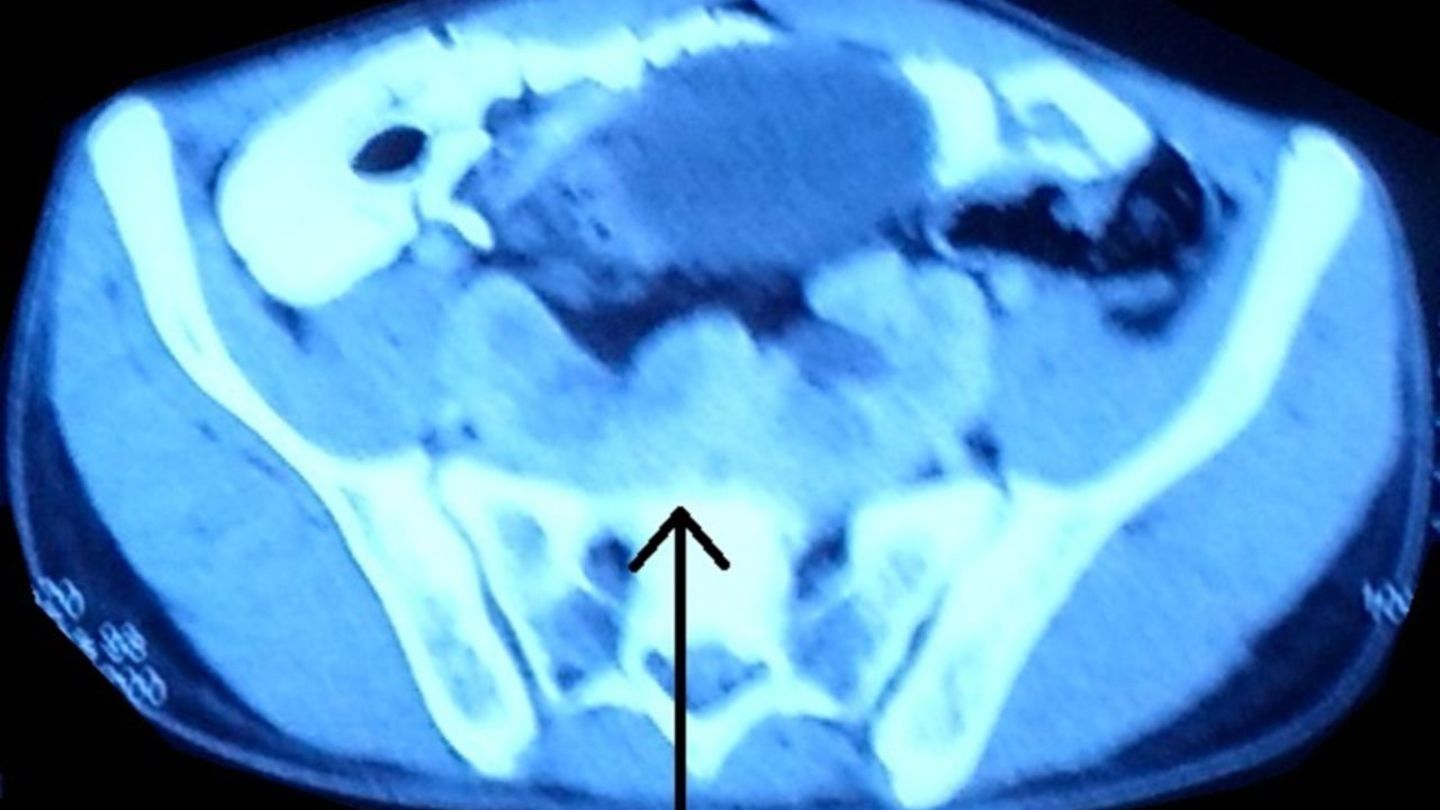

Auf den Aufnahmen ist deutlich zu erkennen, dass die Nieren des Mannes in der Mitte zusammengewachsen sind. In Fachkreisen wird diese angeborene Fehlbildung auch als "Pfannkuchen-Niere" bezeichnet. Der Name dürfte in erster Linie der Optik zuzuschreiben sein: Die Nieren sind verschmolzen und erscheinen wie eine einzelne flache Masse.

Wie das Ärzteteam im Fachblatt "BMJ Case Reports" schreibt, handelt es sich dabei um eine "extrem seltene" Fehlbildung, die in der frühen embryonalen Entwicklung passiert. Grundsätzlich lassen sich mehrere Formen von Nieren-Fehlbildungen unterscheiden. Die Pfannkuchen-Niere macht weniger als zehn Prozent aller Fälle aus.